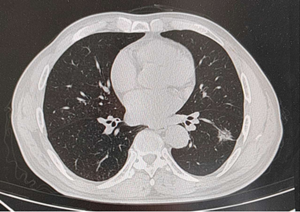

患者是一位65岁男性,因“查体发现左肺下叶结节病变3天”入院,胸部CT示左肺下叶结节,位于背段,大小约2.0×1.8cm,边缘见毛刺及分叶,邻近胸膜略增厚、牵拉。胸外科团队经过充分讨论后,决定给予实施“单孔胸腔镜下左肺下叶切除加系统性淋巴结清扫术”。手术过程顺利,患者目前术后恢复顺利。

胸部CT示左肺下叶结节灶